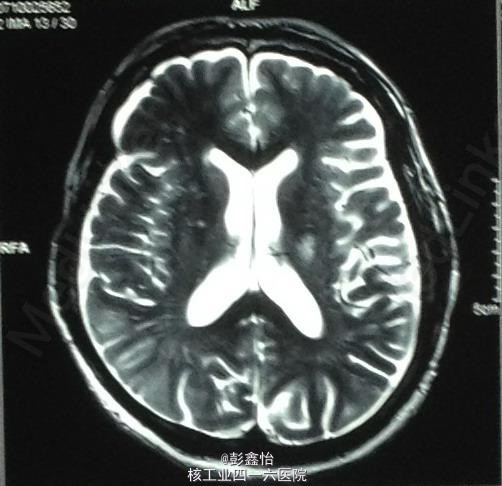

PE: NE:神经专科查体均正常; ABCD2评分为3分 NIHSS评分为0分; 入院后辅助检查均正常,CT、MRI+MRA、脑电图、视频脑电监测均未见异常。

因患者无明显肢体抽搐及局部泛化过程,脑电监测正常,基本可除外癫痫发作。诊断TIA,予以阿司匹林、他汀降脂等治疗,但TIA继续发作。 追加血管评估,但TCD、DSA、颈部血管超声均未发现异常,在原有治疗基础上,予以双抗、改善循环、营养神经加强治疗 但患者仍频繁发作TIA,3天内共发作20余次。判断为治疗抵抗,继续加用抗凝、脑保护,最后加用羟乙基淀粉扩容治疗后发作终止,但患者出现右侧肢体轻偏瘫。 复查DWI:左侧基底节区出现急性梗死灶; 复查MRA、DSA均未见异常。